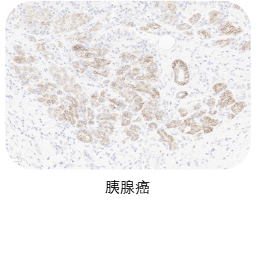

★ 验证充分:三阴性乳腺癌、前列腺癌、胰腺癌、卵巢癌、皮肤癌临床样本充分验证

❷ 适应症癌种染色

选取肿瘤组织样本用于敏感性染色,TROP2一抗染色阳性细胞细胞质和/或细胞膜特异性阳性着色(染色强度≥1),无非特异性着色(染色强度<1),无背景染色(染色强度<1 )。

ACRO IHC实验室目前已建立了成熟的TROP2染色方法与判读体系,适用三阴性乳腺癌、前列腺癌、胰腺癌、卵巢癌、皮肤癌等多个癌种,可快速用于相关肿瘤的临床试验入组筛选与样本检测,部分结果展示如图所示。